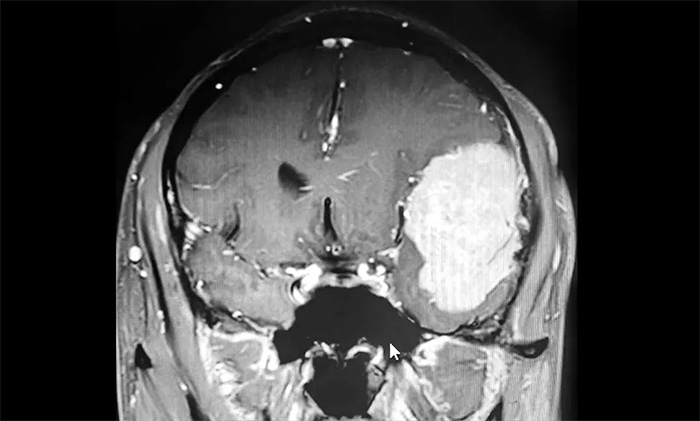

男子罹患鸭蛋大脑肿瘤一度脑疝危及生命 神经外科沈建康、于耀宇主任团队全力救治化险为夷

脑胶质瘤是常见的颅内恶性肿瘤,往往生长较快,可在短时间内造成颅内压增高和占位效应,引起一系列严重的神经系统症状,甚至可因脑疝危及生命。因此,一旦出现剧烈头痛、肢体偏瘫、嗜睡时,应高度警惕,尽...【详细】